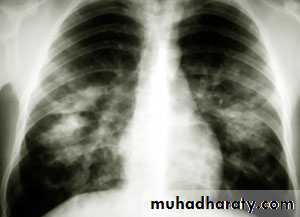

Lobar pneumonia: homogenous consolidation of one or more lung lobes, often with associated pleural effusion

A chest X-ray is usually sufficient to confirm the clinical diagnosis of pneumonia.

In lobar pneumonia, a homogenous opacity localized to the affected lobe or segment usually appears within 12 – 18 hours of the onset of illness.

Chest X-ray helps in:• Differentiating CAP from other diagnosis

• Provide information about severity (cavitation and multilobar involvement)

• Detects complications (pleural effusion or abscess formation).

• It can occasionally suggest an aetiological agent (pneumatocoele in Staphylococcus aureus pneumonia).